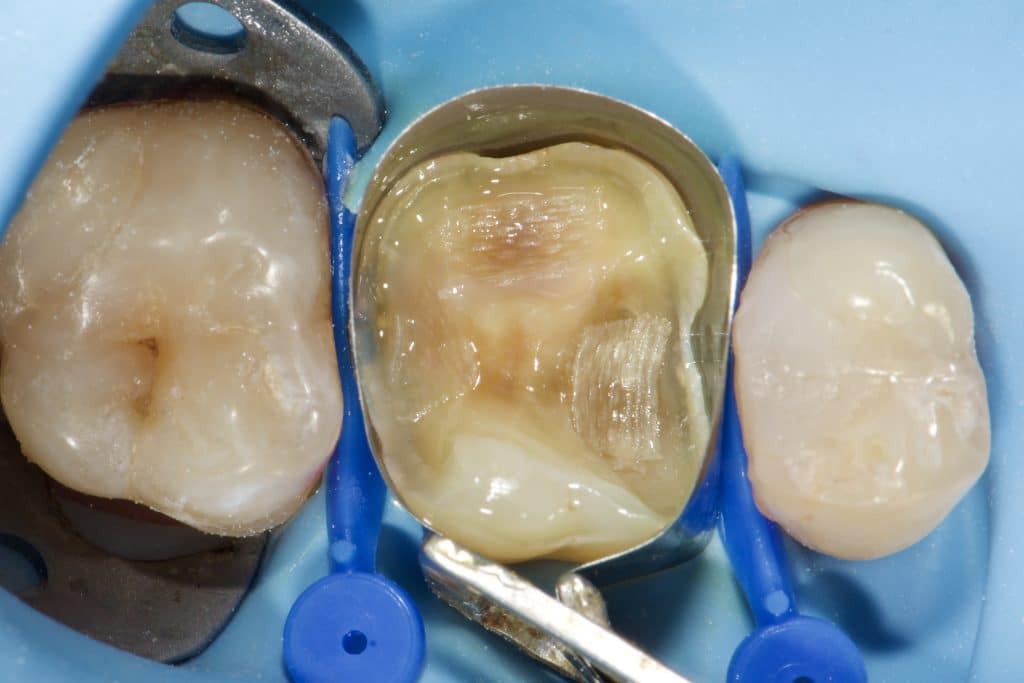

“Can a direct composite overlay function as effectively as an indirect lithium disilicate restoration? Composite restorations, once used as a long-term temporary solution for badly damaged molars, are now considered permanent. While the composite material remains the same, our understanding of its adhesive and physical properties has evolved. The procedure may be more time-consuming and require multiple stages in the same visit, depending entirely on the dentist’s skills.